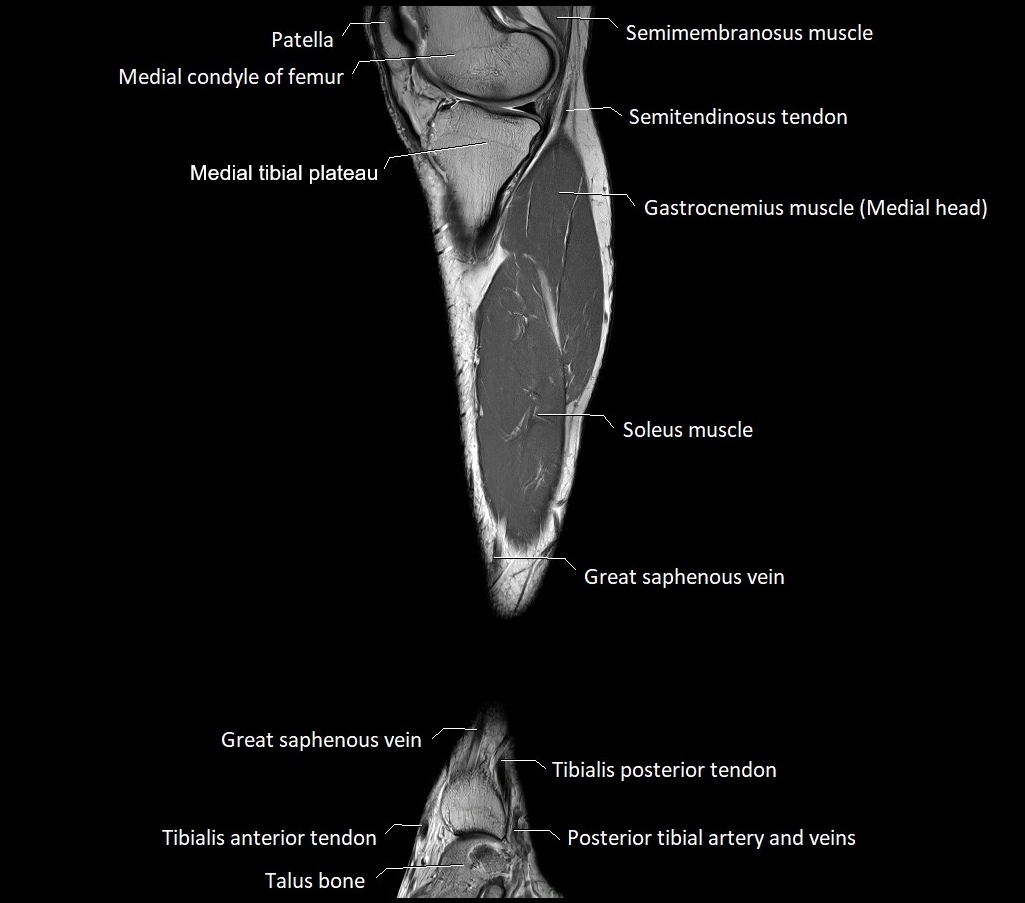

MRI image